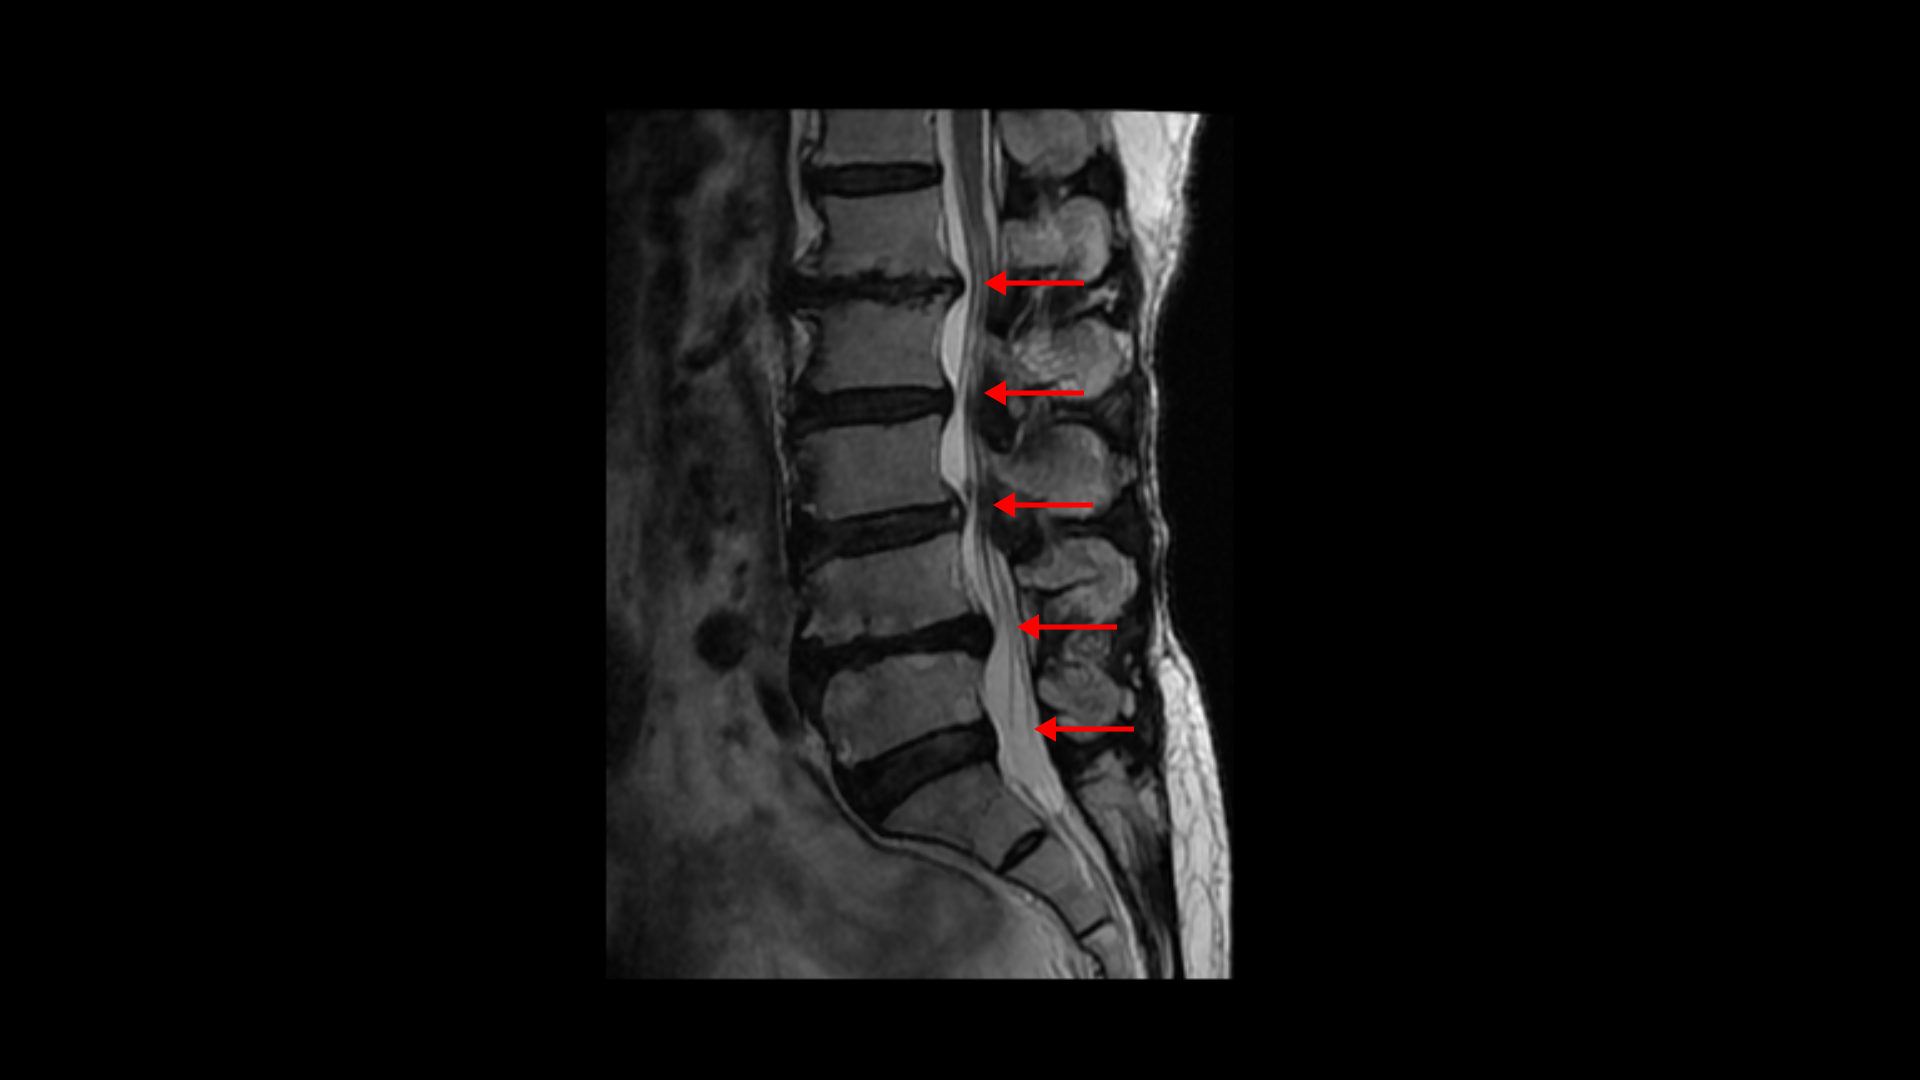

이분 MRI를 보면 허리 다섯 마디에 전부 퇴행성 디스크가 있습니다.

1-2번에는 오른쪽으로 디스크도 밀려 나와 있고 중심성 협착도 있습니다.

2-3번에는 왼쪽으로 신경구멍 쪽으로 디스크가 밀려 나와있습니다.

3-4번에는 중심성 협착이 있고

4-5번에는 왼쪽으로 디스크가 밀려 나와있고 심한 중심성 협착과 왼쪽 추간공협착도 있습니다.

5-1번에는 왼쪽으로 디스크가 밀려 나와있고 전반적으로 왼쪽이 상태가 더 안 좋은데 이분의 증상도 왼쪽 엉덩이와 다리의 통증과 저림 및 마비감입니다.